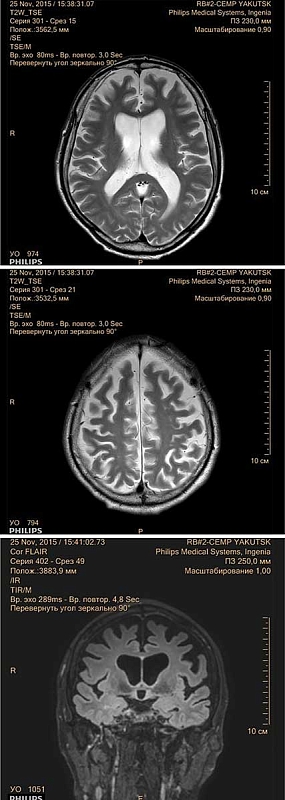

Рис. 3. Пациент П.: МРТ головного мозга от 25 ноября 2015 г.

МРТ от 30 августа 2000 г.: выраженная атрофия головного мозга.

МРТ от 26 августа 2011 г.: явления диффузной церебральной атрофии мозга. Разомкнутый виллизиев круг с дорзальной трифуркацией справа. Данных об аневризме нет. Значительное равномерное расширение желудочков мозга без признаков избыточного давления и перивентрикулярного отека. Мозолистое тело истончено. Выраженное равномерное расширение конвекситальных пространств в лобно-теменно-височных отделах полушарий большого мозга и в области полушарий мозжечка.

МРТ от 25 ноября 2015 г. (Ingenia, PHILIPS, с дополнительным внутривенным введением гадолинийсодержащего контрастного препарата) (рис. 3): диффузное расширение субарахноидальных пространств суб- и супратенториальных отделов головного мозга. В белом веществе лобно-теменных долей с обеих сторон множественные мелкие очаги лейкопатии. После внутривенного введения контрастного препарата очагов патологического накопления не выявлено.